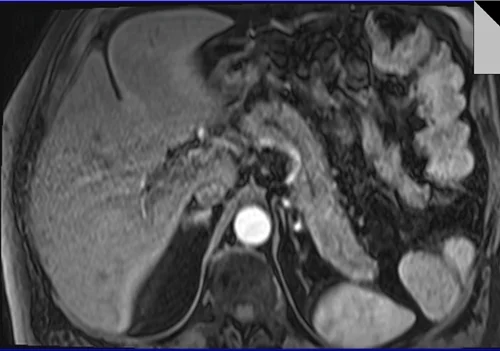

VIBE FAT SAT AXIAL POST CONTRAST SEQUENCE USED IN LIVER IMAGING